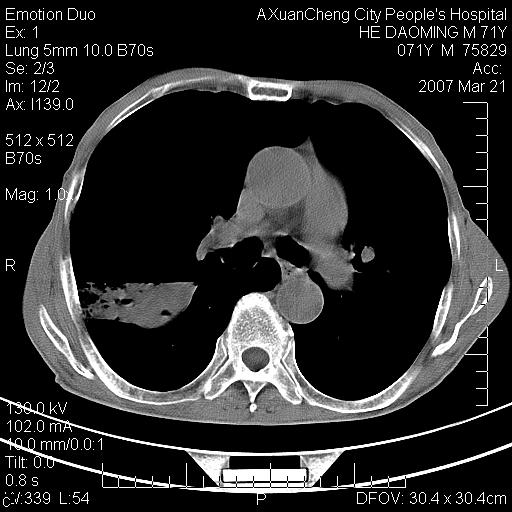

标题: CT7269:[原创] 咳嗽,咳痰,大家讨论右肺病变的部位 [打印本页]

标题: CT7269:[原创] 咳嗽,咳痰,大家讨论右肺病变的部位

右侧相当于叶间软组织样密度ct值约50hu,请大家讨论是什么性者病变

考虑:慢性支气管炎合并全小型肺气肿、肺大泡、间质纤维化、感染,右斜裂积液。

慢性支气管炎,全小叶性肺气肿,右肺上.中叶肺大泡,伴有感染.支气管扩张.

考虑慢支,肺气肿,肺大泡,间质纤维化;右侧斜裂液气胸考虑(可能因为肺大泡破裂破入斜裂所致).

考虑:慢性支气管炎合并右侧全小型肺气肿、肺大泡并感染、双肺间质纤维化,右斜裂积液。

如果患者变化一下体位扫描可分辨液平与斜裂的关系。